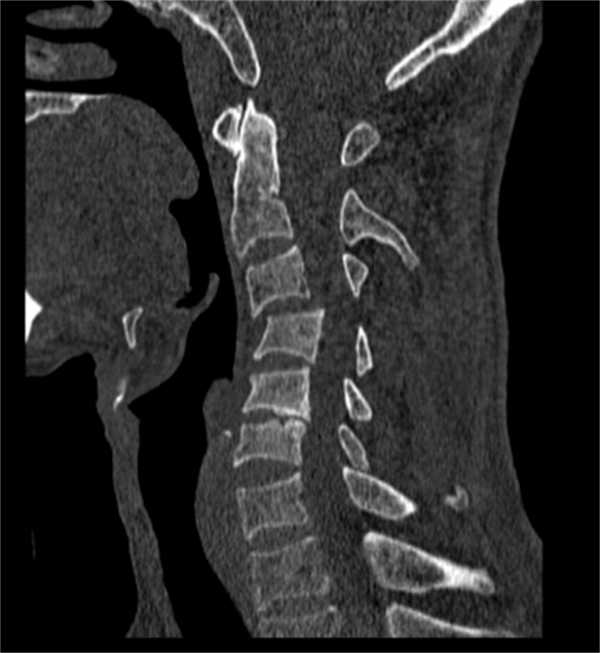

近日,61岁的刘伯(化名),不慎从高处坠落,当即颈部剧痛,颈部活动严重受限,合并有四肢肌力减退,其中右上肢不能抬起,双手活动无力。在当地医院CT检查提示存在颈椎骨折脱位,因伤情急重复杂,刘伯及家属慕名立刻转来萍乡市第二人民医院脊柱外科就医。

术前

市二医院脊柱外科完善相关检查之后诊断为“颈椎骨折脱位合并脊髓损伤,不完全性瘫痪”。该患者第3颈椎骨折伴有双侧关节突脱位交锁,颈椎移位直接压迫脊髓导致不完全性瘫痪,属于颈椎损伤中的严重类型。因颈椎骨折脱位的节段高,如不能迅速复位解除颈髓的压迫并恢复颈椎稳定性,则会导致患者瘫痪症状加重甚至危及生命。